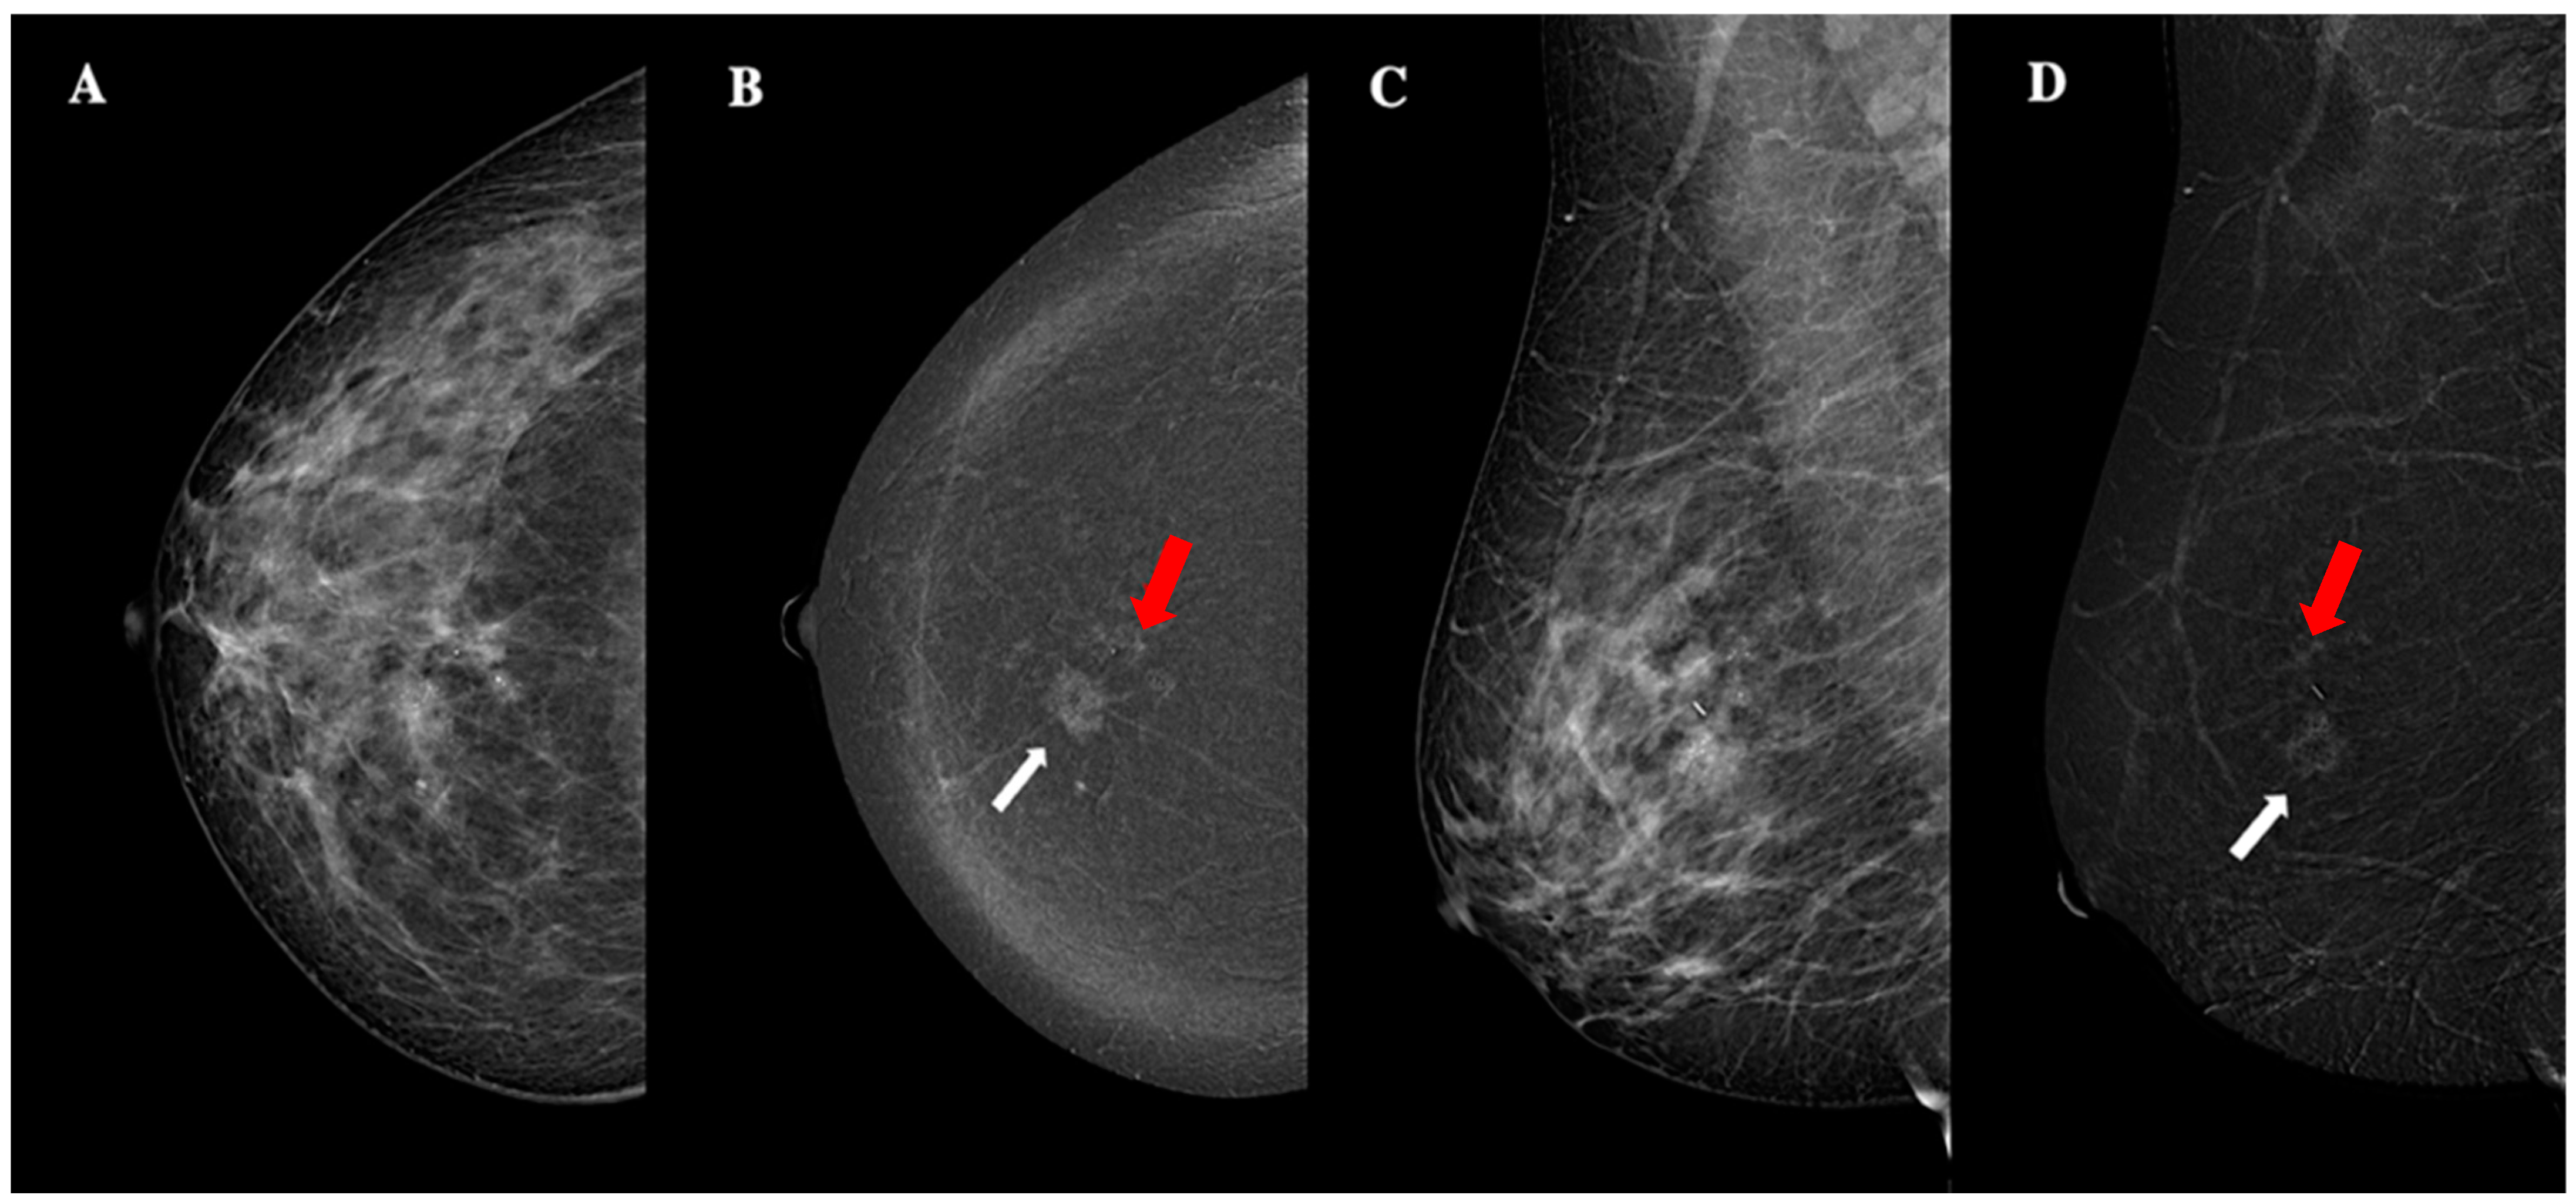

| Lesion enhancement conspicuity | Low (n, %) | 25 (50%) |

| Moderate (n, %) | 10 (20%) | |

| High (n, %) | 15 (30%) | |

| Background parenchymal enhancement | Minimal (n, %) | 26 (52%) |

| Mild (n, %) | 15 (30%) | |

| Moderate—marked (n, %) | 9 (18%) |

| Non-circumscribed margins | Luminal-B | Significant association (p = 0.001) |

| High lesion conspicuity | Luminal-B (n, %) | Significant association (p = 0.001) |

| Triple-negative (n, %) | Significant association (p = 0.001) | |

| Tumor size | Positive correlation (ρ = 0.517, p < 0.001) | |